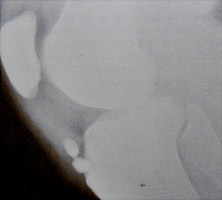

Osgood-Schlatter's disease involves the tibial tubercle. It commonly occurs in adolescent boys. The diagnosis is made on clinical grounds and is characterized by swelling and pain. Radiographically, fragmentation of the tubercle is seen along with elevation away from the shaft.

- Click on the image for a larger versionALateral radiograph of the knee. The tibial tubercle is fragmented in this young male patient. This is the radiographic appearance of Osgood-Schlatter's disease.